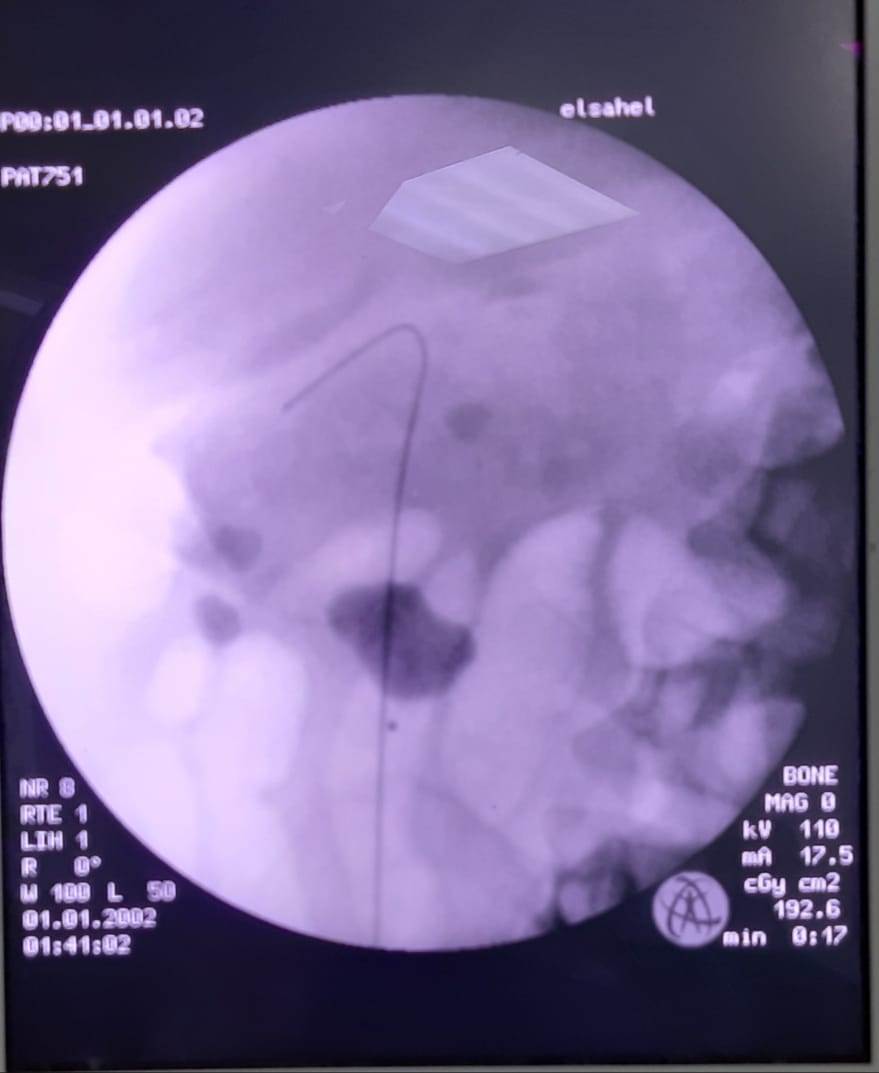

ونجح فريق طبي متخصص فى إنقاذ حياة مريض فشل كلوي مصاب بالكورونا المستجد، بإجراء منظار جراحي وتركيب دعامتين بالحالبين.

وأضاف أن المريض الآخر تم حجزه بالمستشفى جراء إصابته بفيروس كورونا المستجد، بالإضافة إلى أنه يعاني من فشل كلوي حاد، نتيجة لانسداد حوض الكليتين بحصوات متشعبة، مما استدعى ضرورة التدخل الجراحي العاجل، وعمل منظار جراحى وتركيب دعامتين بالحالبين لإنقاذ حياته، وقام بإجراء العملية فريق طبي على أعلى مستوى من الكفاءة والمهارة، بقيادة د. محمد الإتربى استشارى المسالك البولية بالمستشفى، ود. يوسف أبو الخير، ود. علي فؤاد، والتخدير د. أحمد حامد الداودي، ود. أندرو مهنى فارس، والمريض حالته مستقرة ويخضع للملاحظة على مدار الساعة.